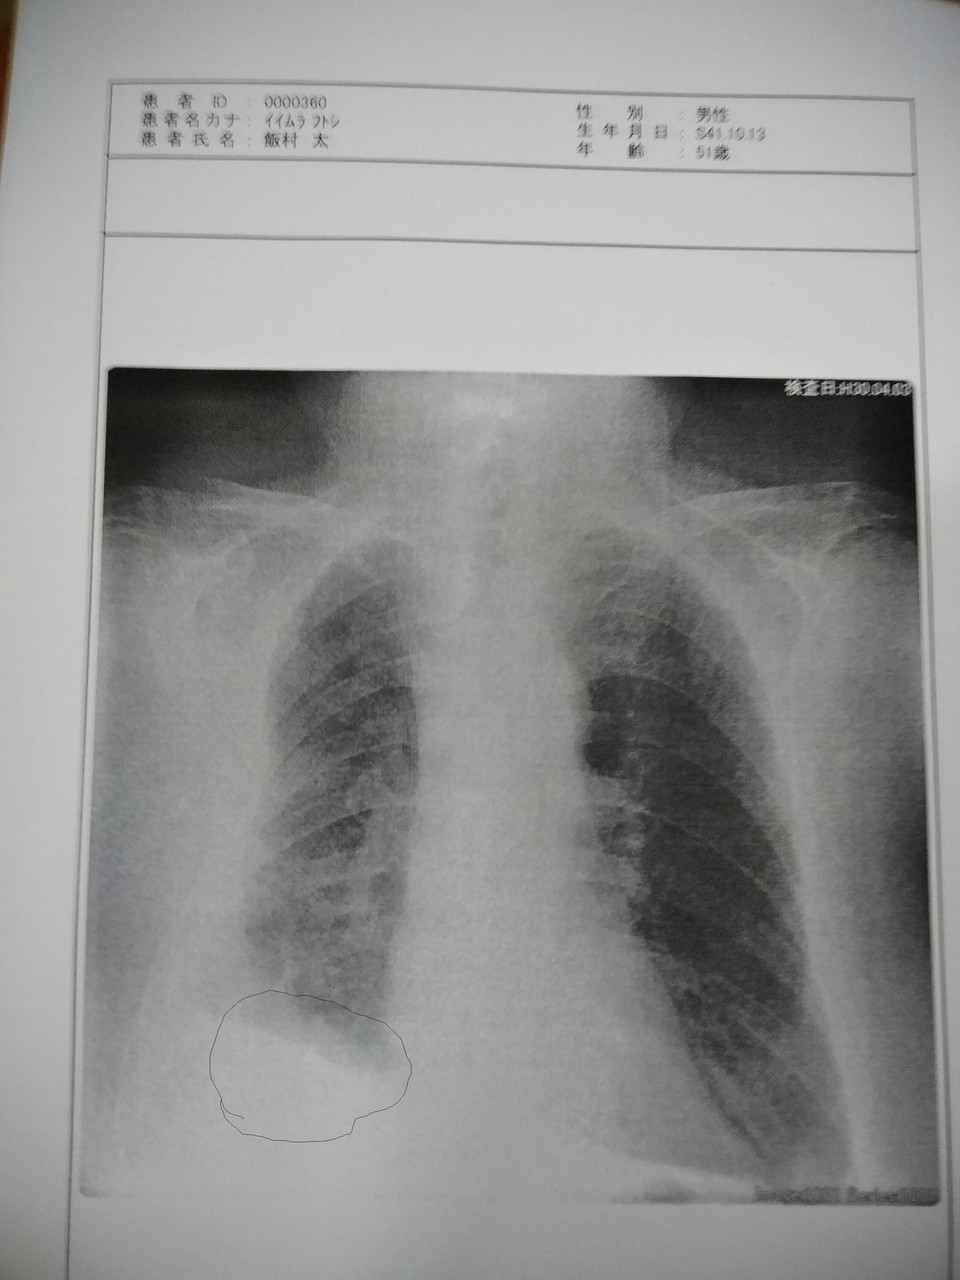

ここぞとばかりに血圧の事を相談したら、「じゃ取りあえずDW上げるにも胸水の事もあるので今日終わったらレントゲン撮ってみましょう。横になって撮ってみて、それで対処しなきゃいけない水かどうか見ましょう」となった

結果は仰向けで撮っても立って撮った時と変わらずに水が動いて無く背中の方とかに行かないらしい

比べた写真も2つとも影の部分が全く一緒

立って撮った写真

寝て撮った写真

左下の丸く囲った部分の水が動いて無いと言う事らしい

「この水の事はあんまり考えなくてもいいかもしれませんねぇ。でも一応呼吸器内科で1度CT撮って見てもらった方がいいかもしれません」と言う事で予約を入れてもらう事になった